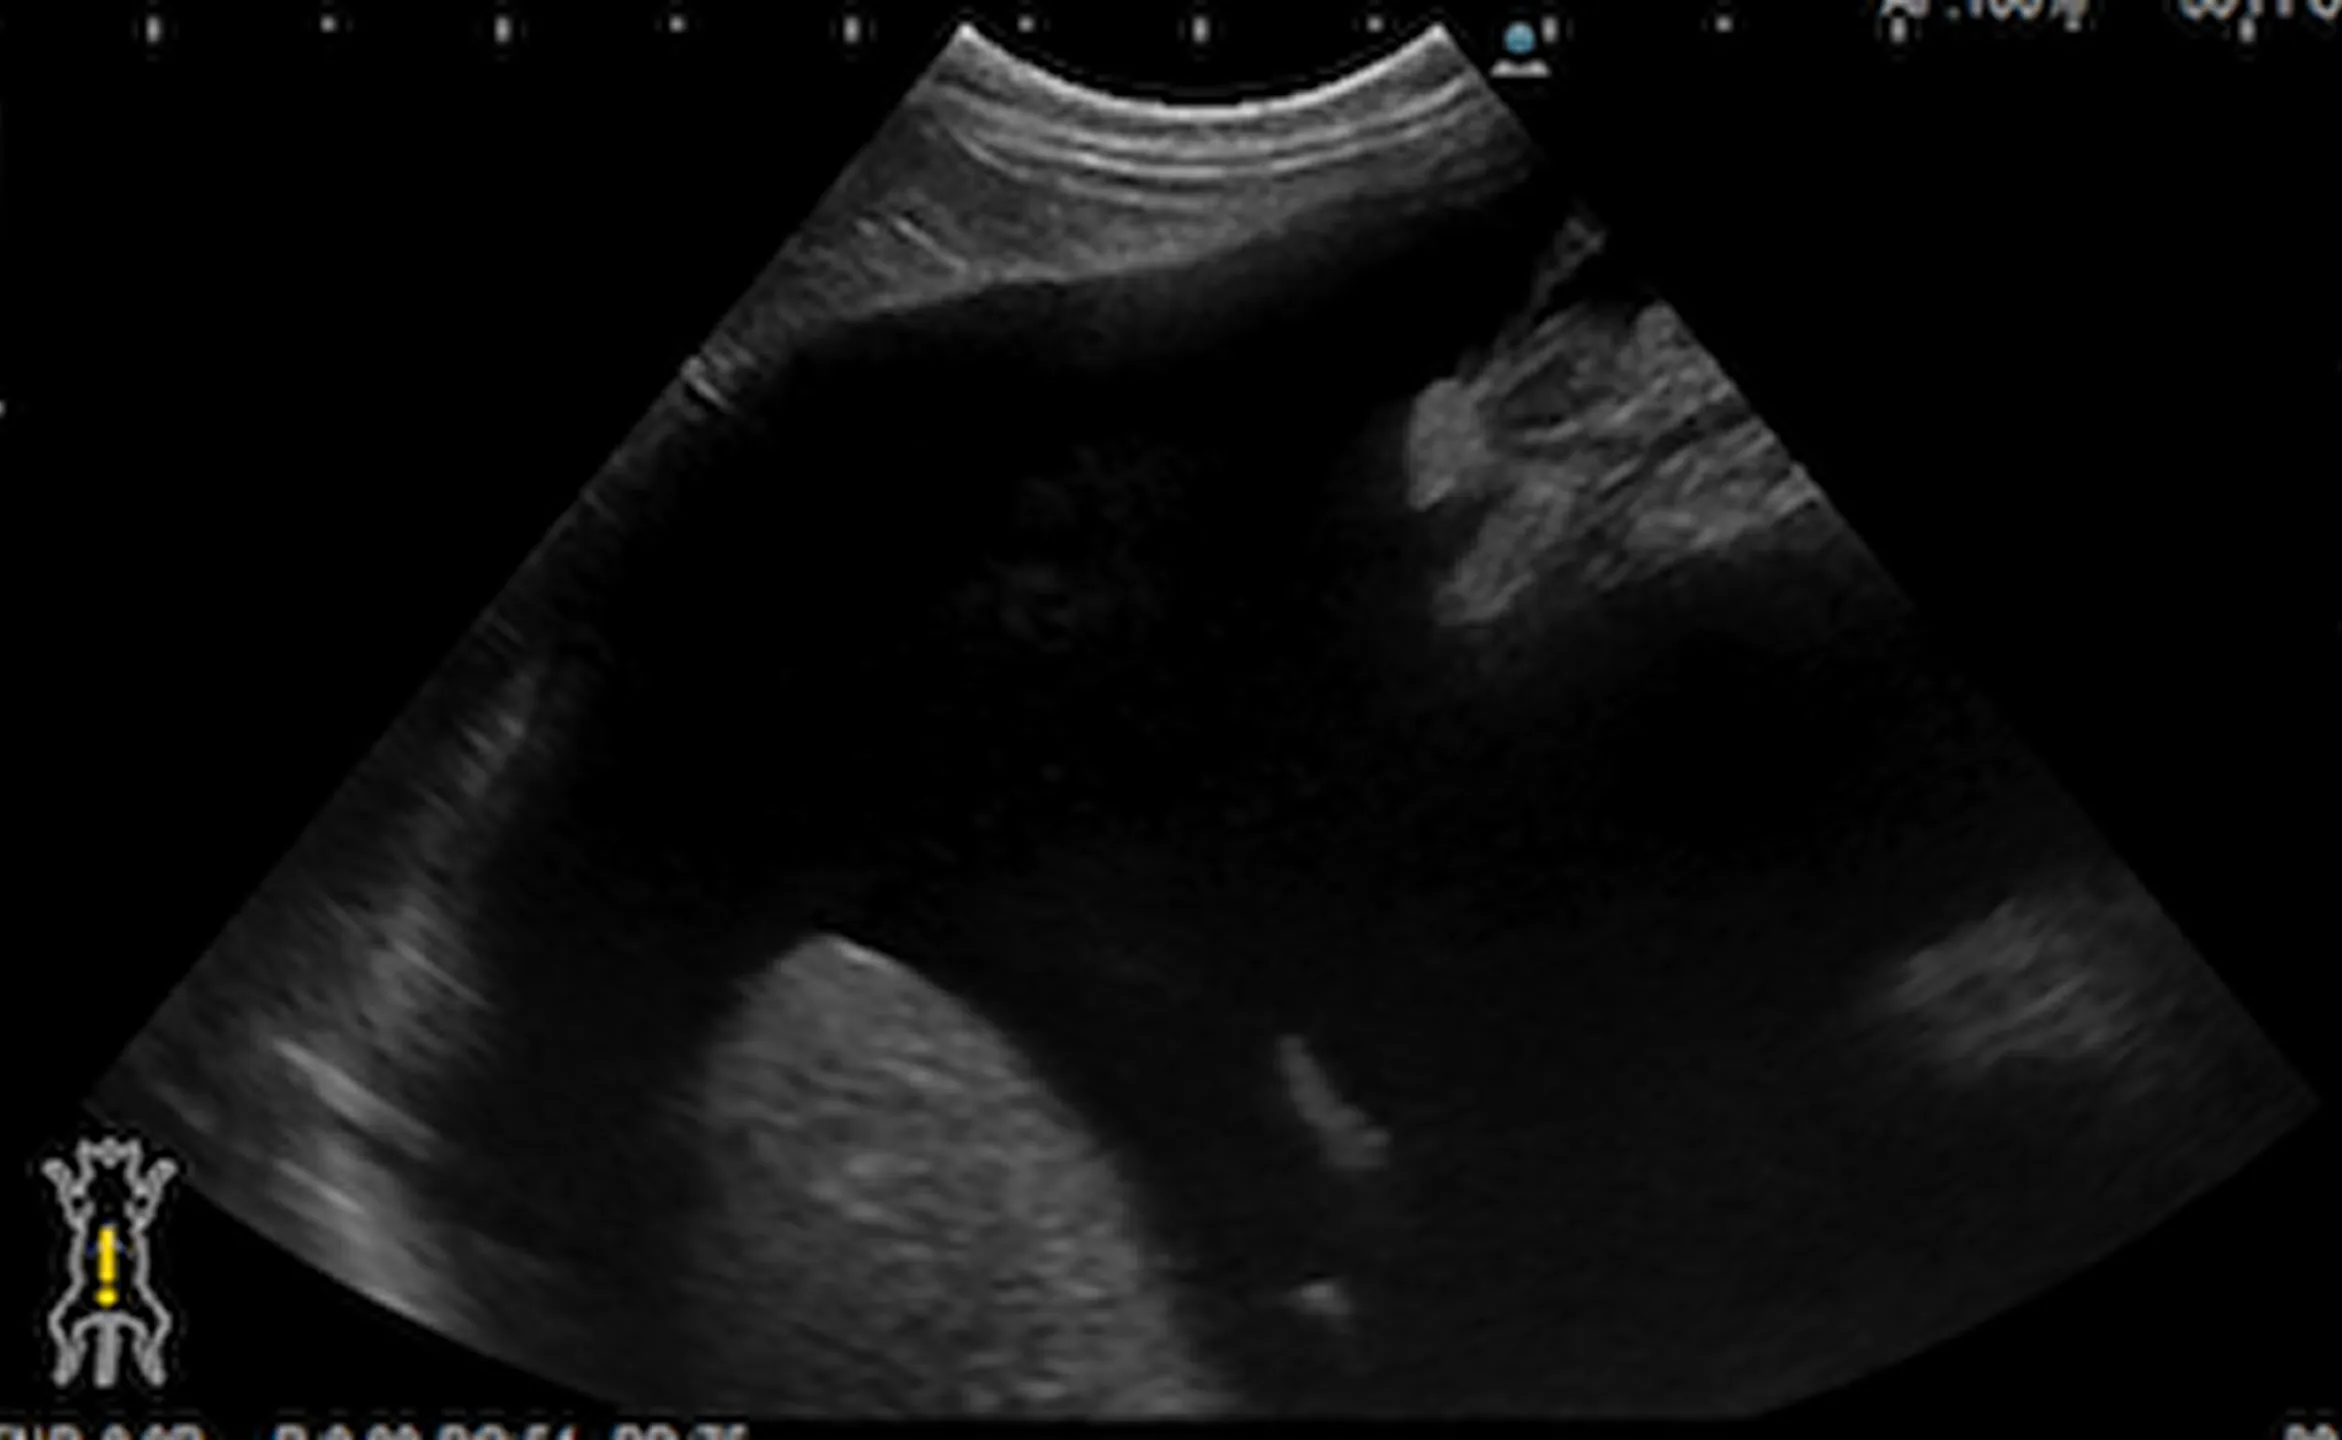

治療前後の超音波検査画像

治療前

黒く見えているところが腹水です。